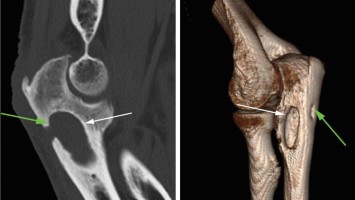

Unklare Raumforderung der proximalen Ulna

Ein 57-jähriger Metzgermeister stellte sich mit seit 20 Jahren wiederkehrenden linkseitigen Ellenbogenschmerzen vor. Bei uneingeschränktem Bewegungsumfang fiel in der klinischen Untersuchung lediglich ein geringes, positives Cozen-Zeichen sowie ein dezenter Druckschmerz über dem M. anconeus auf. Erkennen Sie die Ursache?